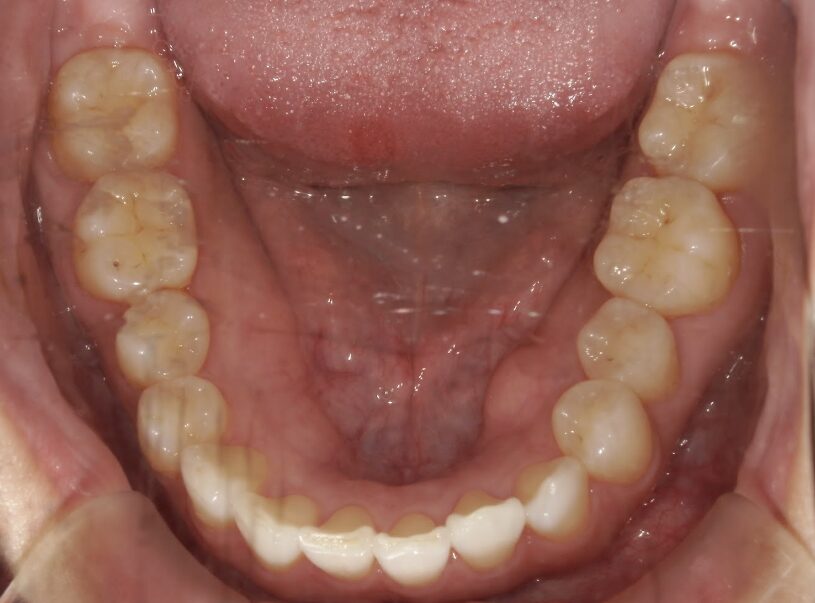

過蓋咬合

治療前

ガタガタを主訴に当院を受診され、上下前歯部に叢生(ガタガタ)と過蓋咬合(上の歯が下の歯を深く覆いかぶさっている状態)を認めました。